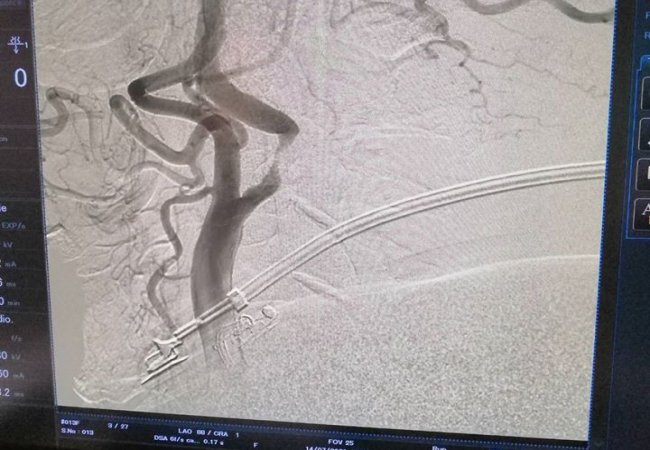

Зазначаєтся, що 53-річний пацієнт звернувся за медичною допомогою зі скаргою на часті втрати свідомості.

І вже після додаткових обстежень лікарі виявили, що просвіт обох внутрішніх сонних артерій був значно звужений – більше зліва до 95%.

Тож хірурги Ковельського МТМО успішно провели стентування (внутрішньої сонної артерії) зліва. Стент, який був використаний для проведення операції, відновив звичний діаметр судини та відповідно кров у більшому об'ємі почала надходити до головного мозку.

Тож стан пацієнта значно покращився. Проте його чекає ще одна операція.